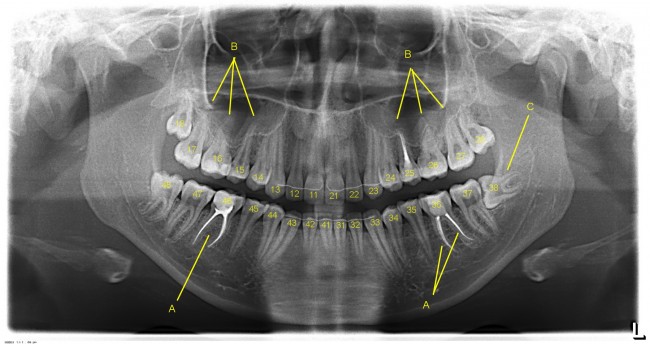

Многие об этом забывают, но в дентальной имплантации расходниками являются, в том числе, инструменты для подготовки лунки и установки имплантата. В частности, спиральные и лепестковые фрезы для препарирования костной ткани имеют ресурс 20-50 рабочих циклов, по истечении которого они выходят из строя: